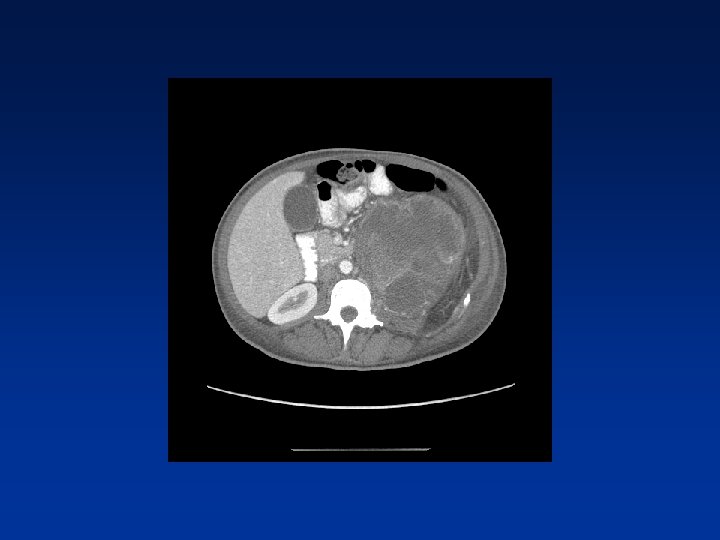

CASE